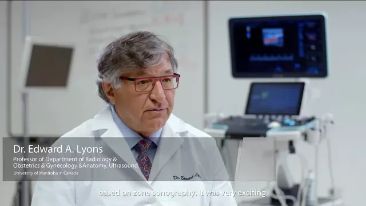

Resona 7

Nuevas ondas en la innovaciÃģn de ultrasonido

Desde su creaciÃģn, Mindray no ha dejado de explorar nuevas maneras de mejorar la fiabilidad del diagnÃģstico. Gracias a ZONE Sonography?, la tecnologÃa mÃĄs revolucionaria, la nueva plataforma ZST+ del Resona 7 eleva la calidad de imagen de ultrasonido mediante la adquisiciÃģn de zonas y el procesamiento de datos de canal.

AdemÃĄs de una calidad superior de la imagen, el Resona 7 tambiÃĐn mejora las capacidades de investigaciÃģn clÃnica gracias al revolucionario V Flow para la evaluaciÃģn hemodinÃĄmica vascular y la adquisiciÃģn de planos mÃĄs inteligente a partir de un conjunto de datos 3D para el diagnÃģstico CNS fetal. Combinando el funcionamiento multitÃĄctil mÃĄs intuitivo basado en gestos y todas las funciones clÃnicas esenciales, el Resona 7 estÃĄ realmente encabezando nuevas ondas en la innovaciÃģn del campo del ultrasonido.